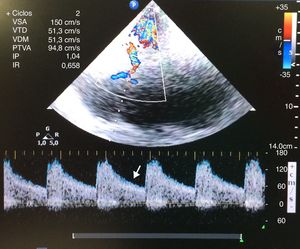

Mujer de 43 años con cefalea brusca. La TC demuestra hemorragia parieto-occipital izquierda sobre lesión subyacente con herniación parcial. La escala de coma de Glasgow (GCS) 15 hasta el 4.° día, en el que presenta anisocoria derecha y GCS 3. Se inicia osmoterapia, sedación, VM, hiperventilación y catéter en subclavia derecha, resolviéndose la anisocoria y siendo el valor de BIS 40 (se descarta resangrado en la TC). A los pocos minutos se implanta sensor de PIC (65mmHg), BIS cae a 0 y el Doppler transcraneal objetiva flujo sistólico con ausencia de onda diastólica (fig. 1), que no revierten con medidas de 1.° nivel. Descartadas otras etiologías de hiperPIC, se realiza Rx de tórax de control de vía, aún pendiente, objetivándose neumotórax (NT) derecho iatrogénico a tensión. Tras drenar NT, se normalizan pupilas, velocidades de la ACM (fig. 2), BIS y PIC.